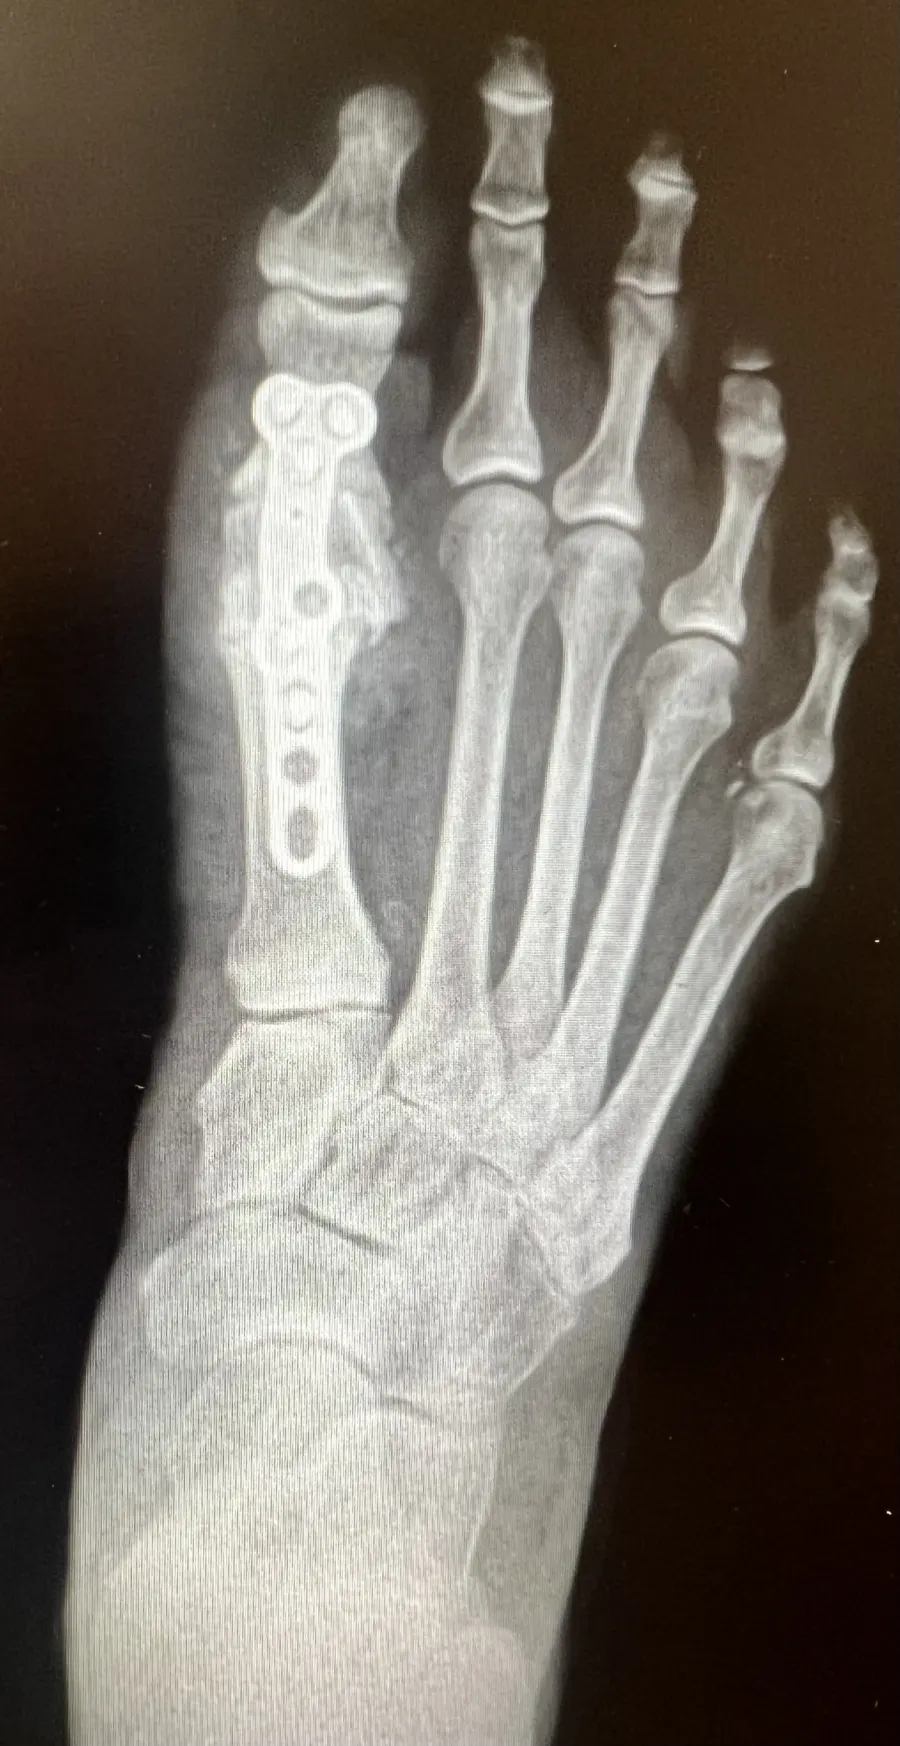

Surgical Intervention at Stepwell Institute is never a “one-size-fits-all” solution. We view surgery as a precise tool used to restore the natural biomechanics of the foot and ankle when non-invasive methods have reached their limit. Our philosophy centers on individualized surgical planning—using advanced imaging to map out the procedure before you ever enter the operating room. From correcting bunions and hammertoes to performing ligament repairs and fracture fixations, Dr. Yakov utilizes techniques designed to minimize trauma to the surrounding tissues, thereby reducing the risk of complications and ensuring a more stable, long-term result for our patients.

Stepwell Institute distinguishes itself by offering NJ patients access to the most advanced surgical modalities in modern podiatry. We specialize in Surgical Intervention, which utilize smaller incisions and specialized instruments to reduce post-operative pain and scarring. For more complex cases, we employ 3D-printed surgical guides and biological grafts to enhance the body’s natural healing ability. By choosing Stepwell Institute, you benefit from a specialized recovery plan where Dr. Yakov and our team prioritize early, safe mobilization. Our goal is to provide a definitive surgical solution that allows you to return to the active New Jersey lifestyle you love with confidence and strength. confidence and strength.

What are some different types of Surgical Interventions?

• Corrective Surgeries

• Reconstructive Surgeries

• Hardware Removal Surgeries

Our Case Study